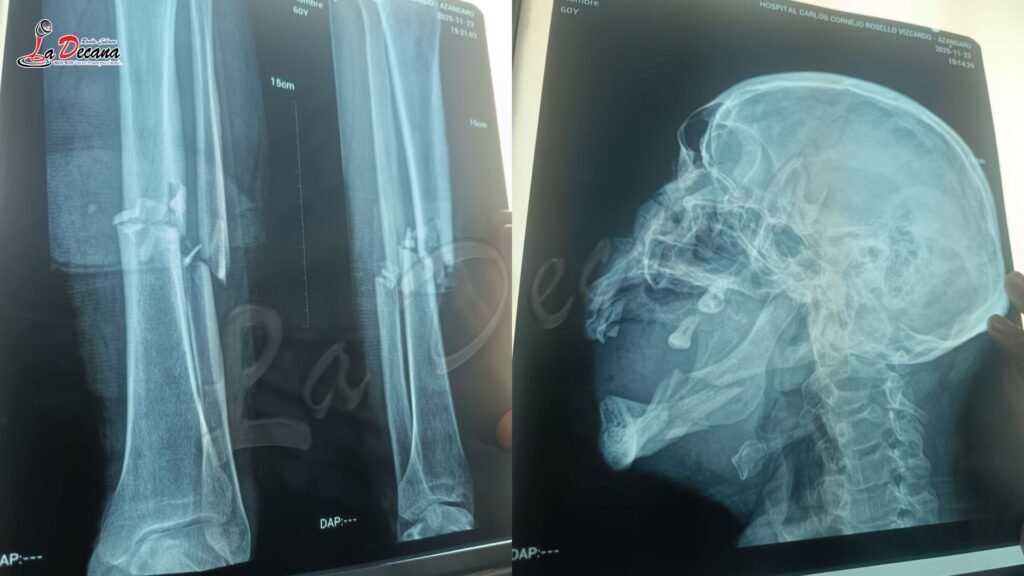

El accidente dejó a la autoridad local con fractura en la pierna izquierda y mandíbula fracturada, lesiones que requieren intervenciones quirúrgicas urgentes.